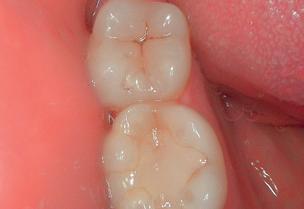

Improved interpretation of tooth shades with rendering of natural colors.

Exclusive macrovision performance

Extreme visibility for ultra-precise diagnosis.

Record of natural colors for a better interpretation of tooth shade, pathology identification and patient follow-up.

High contrasts emphasizing anatomic fissures and details of the dentin structure/depth.

Daylight or Diagnostic aid modes help you visualize anatomical details that are invisible to the naked eye or with a mirror (thanks to its magnification).